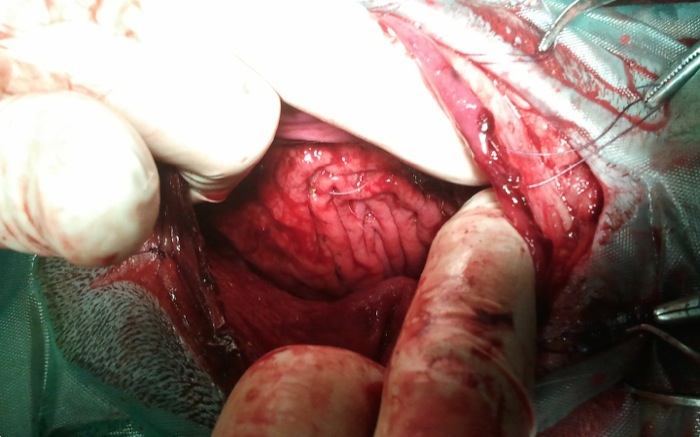

Tras la apertura del estómago se encuentra una cavidad con espuma mojada muy compactada. Se extraen los innumerables pedazos de espuma algunos adheridos a mucosa junto con restos de tejido. Aunque partimos con una taquicardia sinusal ahora nos aparece un bloqueo AV de 2º grado para terminar en un ritmo bigémino que pasa a ventricular durante 2/3 de la cirugía y bradicardia servera pero mayor a 45 lpm. Por su origen no es tratable con atropina.

Tras comprobar que no queda nada, sin olvidar cardias y píloro donde encontramos pedazos encajados, se procede al lavado abundante del interior de estómago con suero a 38º C y su retirada hasta que sale limpio. Hemos pasado de una extrema irritación de mucosa por la acción directa de la espuma durante dos días a un color más fisiológico que permite aventurar una recuperación del paciente.

El cierre re realiza tras cortar el borde de mucosa en el que han ido apareciendo múltiples hematomas a lo largo de la cirugía debido al sufrimiento circulatorio por la impactación y la acción irritante de la espuma durante los días previos.